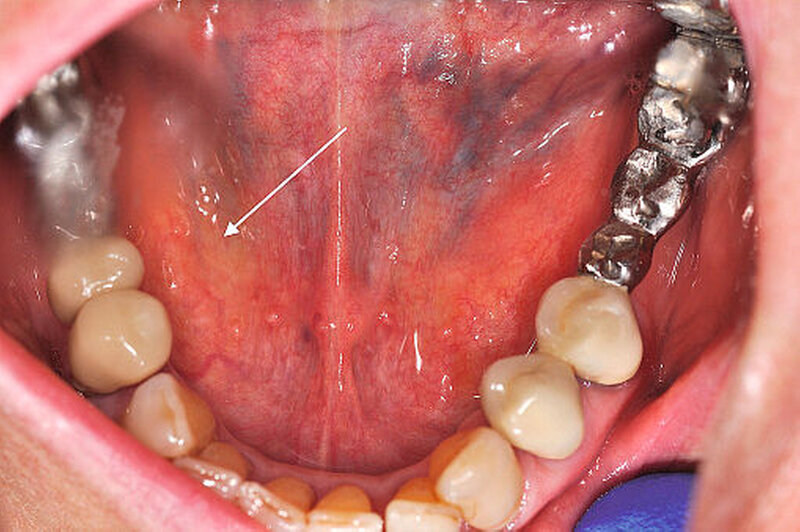

Aufgrund des ausgeprägten Lokalbefunds (Abbildung 2) konnte die Verdachtsdiagnose klinisch durch die bimanuelle Palpation des Mundbodens bestätigt werden. Die Bildgebung mittels Sonografie komplettierte das diagnostische Procedere (Abbildung 3). Nebenbefundlich nahm die Patientin aufgrund von anamnestisch rezidivierenden, tiefen Beinvenenthrombosen Rivaroxaban (Xarelto®, 20 mg, 1–0–0) zur Antikoagulation ein.

Bei klinischem, sonografischem und radiologischem Verdacht auf einen im Ausführungsgang der Glandula submandibularis rechts gelegenen und im hinteren Mundboden lokalisierten Speichelstein, erfolgte nach ausführlicher Aufklärung der Patientin die operative Steinentfernung.